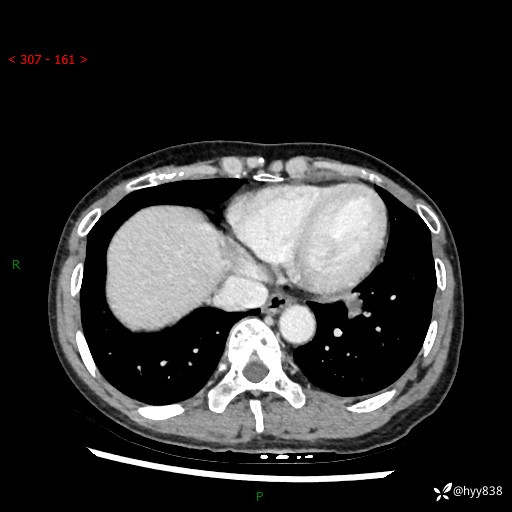

【检查】:胸部CT平扫+增强

各期CT值:40hu 57hu 49hu